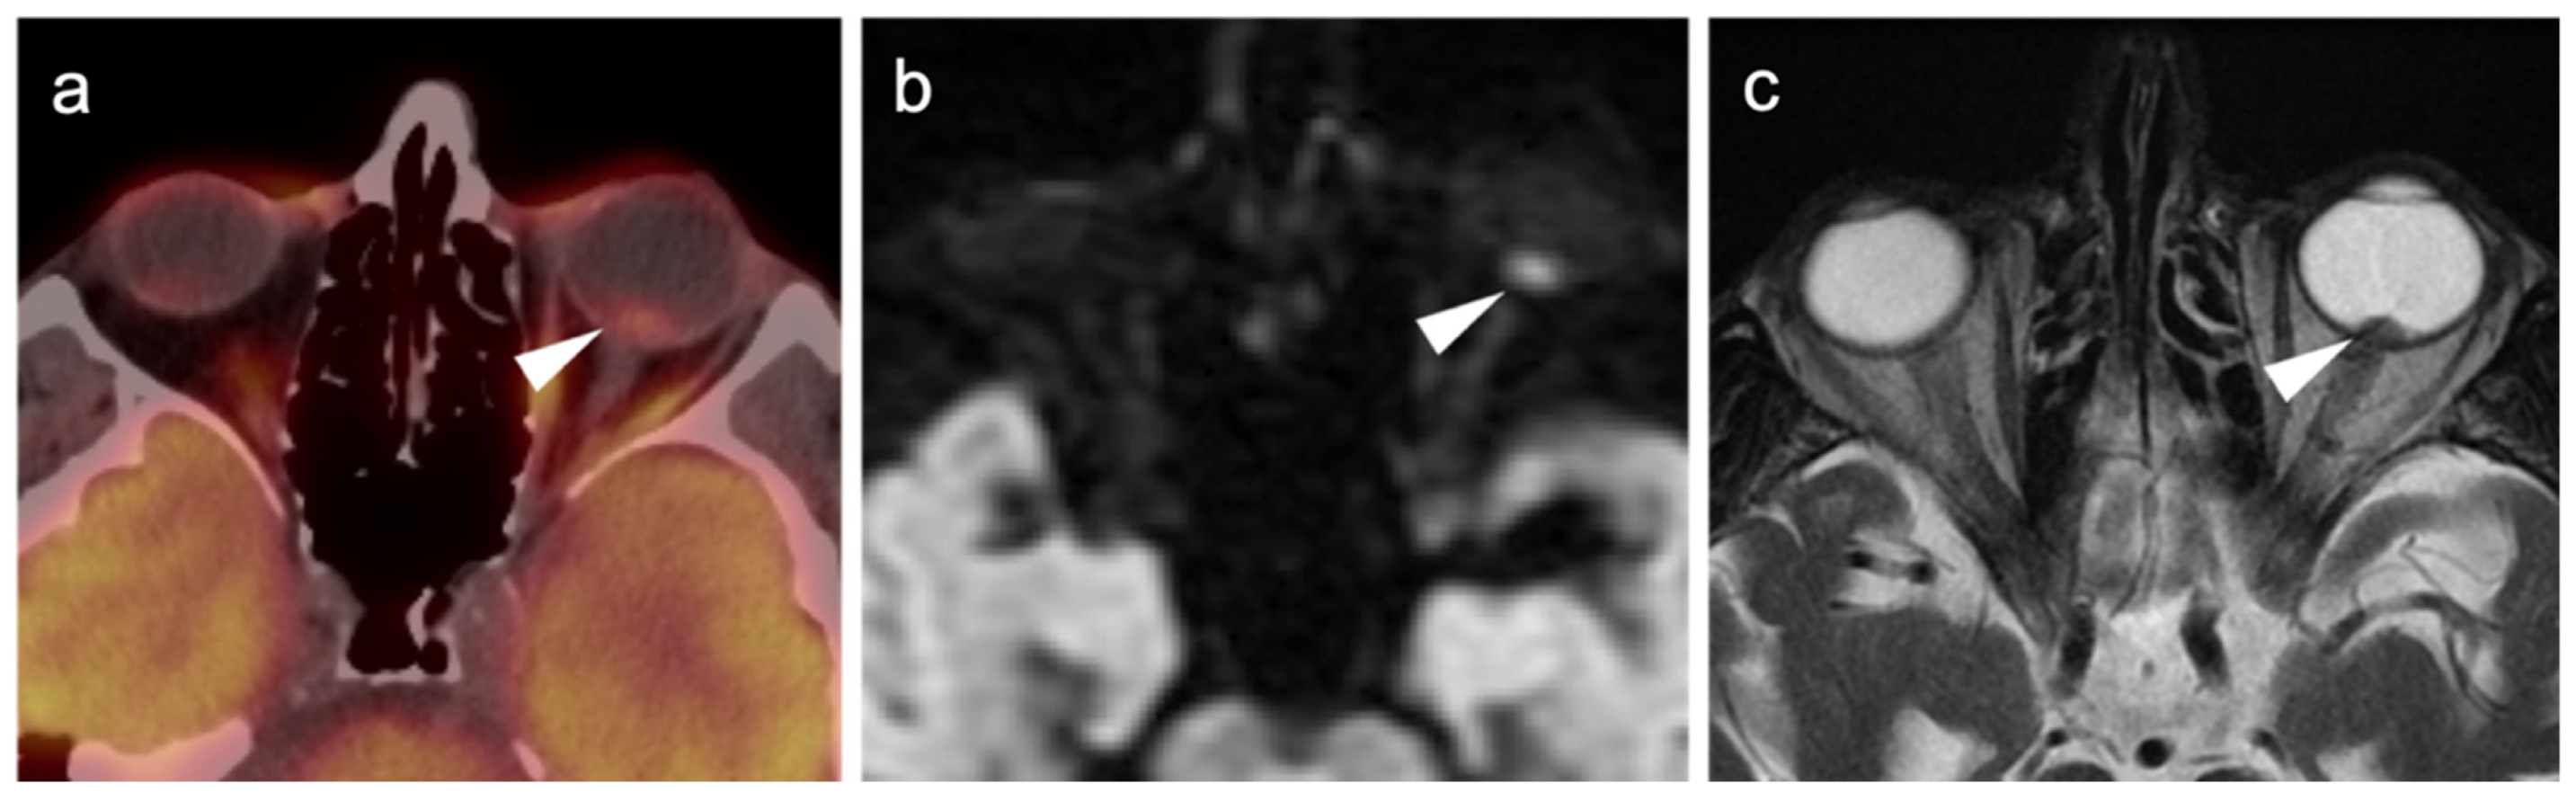

2.3.3. Mucosal Melanoma

2.4. Merkel Cell Carcinoma

2.5. Cutaneous Squamous Cell Carcinoma